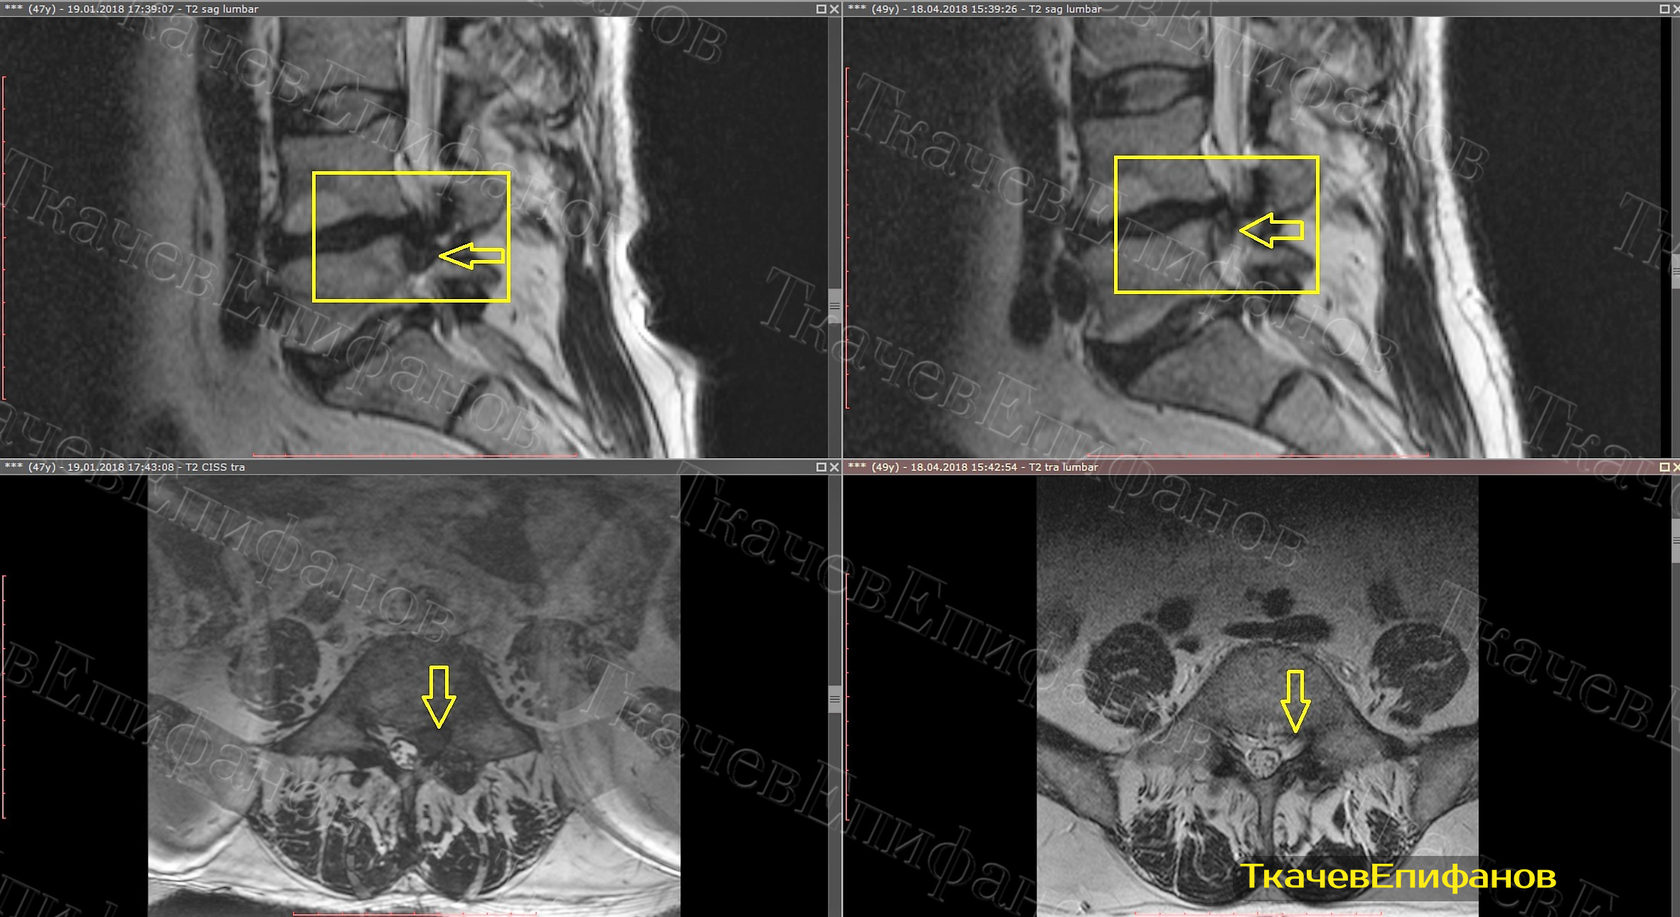

Каудальная миграция диска l4 l5

Каудальная миграция диска l4 l5 113 фотографий